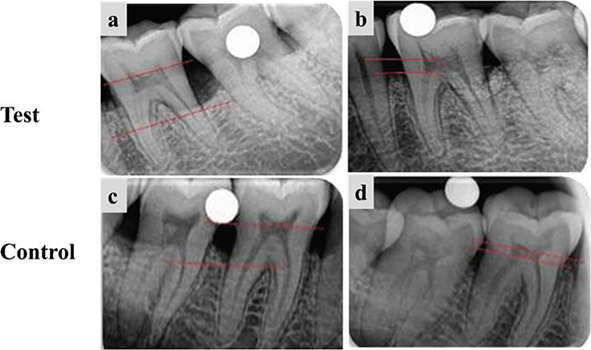

In both groups, mean IBD scores were significantly different at all time intervals (p < 0.05). The intergroup comparison of the mean IBD score was significantly different at 3 months (p = 0.002) and 6 months (p = 0.002), though baseline values did not vary significantly. Similarly, the difference in values from baseline to 3 months (p = 0.0007) and baseline to 6 months (p = 0.004) was significantly different between the two groups (Figure 3 and Table 6).

Figure 3. Radiographic evaluation of the test group and the control group. (a) and (c) Measurement of IBD at baseline, (b) and (d) Measurement of IBD fill at 6 months. IBD: intrabony defects.

Bone fill in the DFDBA group was 45.48%, and in ABC it was 68.63%. This intergroup difference was clinically and statistically significant (p < 0.05).